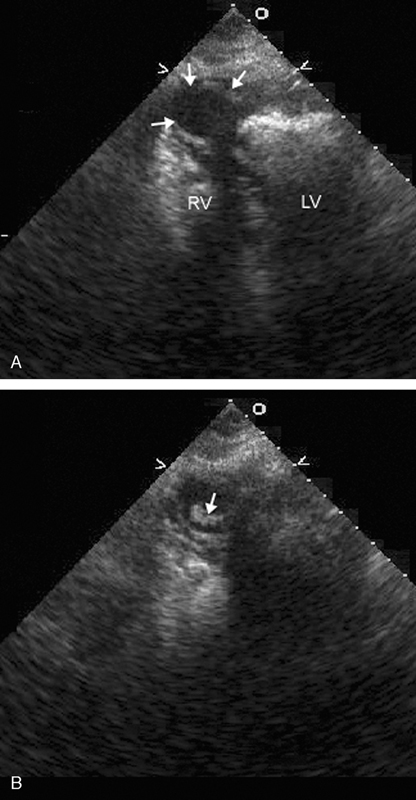

فحوصات تشخيصية لبعض امراض القلب والشرايين التاجية